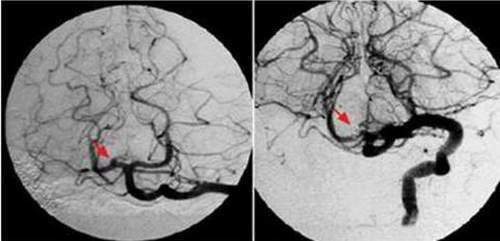

Huyết khối gây tắc mạch làm thiếu máu nuôi vùng não. |

Huyết khối gây tắc mạch làm thiếu máu nuôi vùng não.